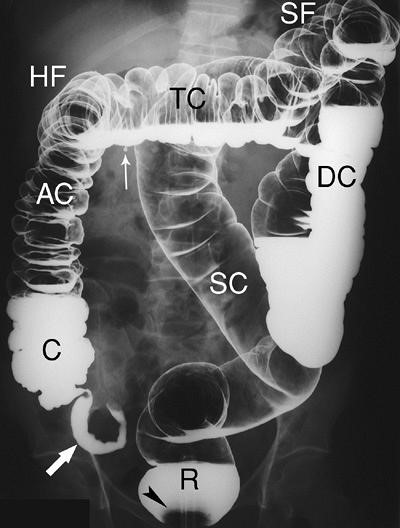

Đại tràng lầ phần cuối cùng của ống tiêu hoá, dài 1,4 m tới 1,8 m [3], gồm có: manh tràng (C) và ruột thừa (mũi tên) ở hố chậu phải, tiếp theo là đại tràng lên (AC) đi sát thành bụng phải tới mặt dưới gan phải, đại tràng ngang (TC) quặt ngang sang trái tới lách, đại tràng xuống (DC) đi dọc thành bụng trái tới hố chậu trái, đại tràng sigma (SC) đi tới chậu hông bé, trực tràng (R) đứng thẳng giữa trước xương cùng. Đại tràng có hai chỗ gấp khúc là: góc đại tràng phải hay góc gan và góc đại tràng trái hay góc lách. Đại tràng lên và đại tràng xuống tương đối cố định.

Các chi tiết giải phẫu X quang bình thường của đại tràng (xem Hình 1 và 2).

Hình 1. Chụp khung đại tràng.